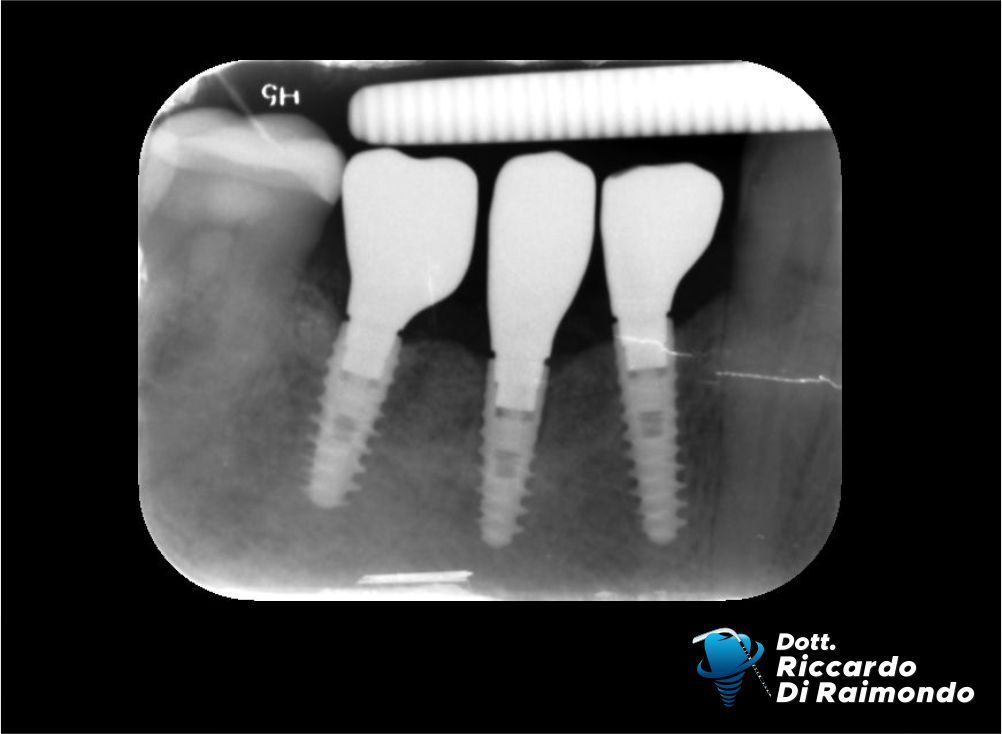

Dopo circa 4 mesi dall’inserimento degli impianti ho finalizzato il caso con la protesi avvitata sugli stessi impianti, restituendo la funzione masticatoria al paziente.

Fine Trattamento